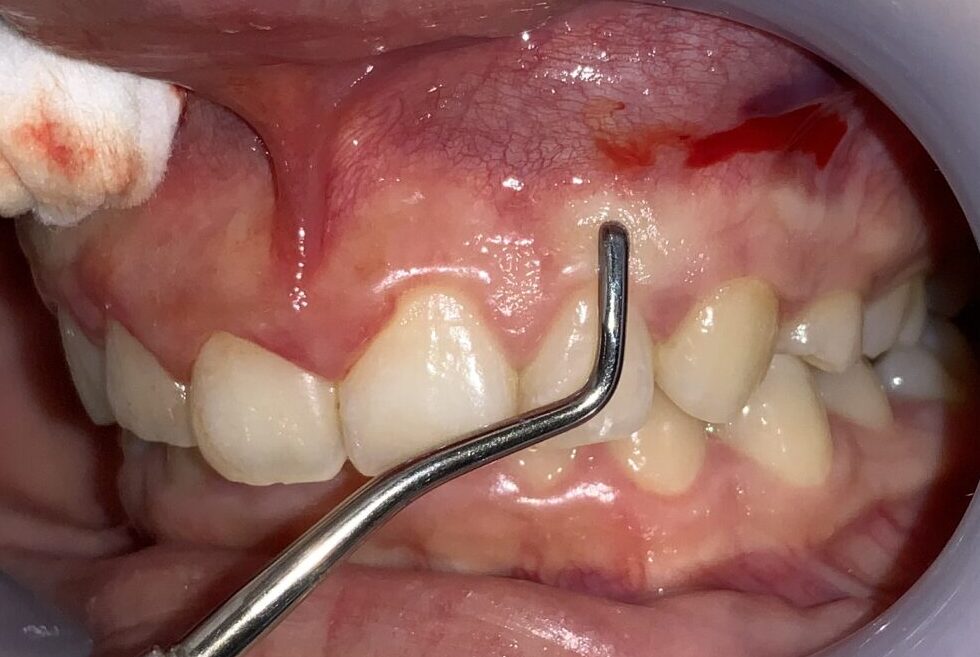

さらに隣の歯も検査します。

こちらの歯は犬歯です。大きく切り取り過ると、八重歯になってしまうので、注意が必要です。

安全に切除できる範囲の歯ぐきを計測します。